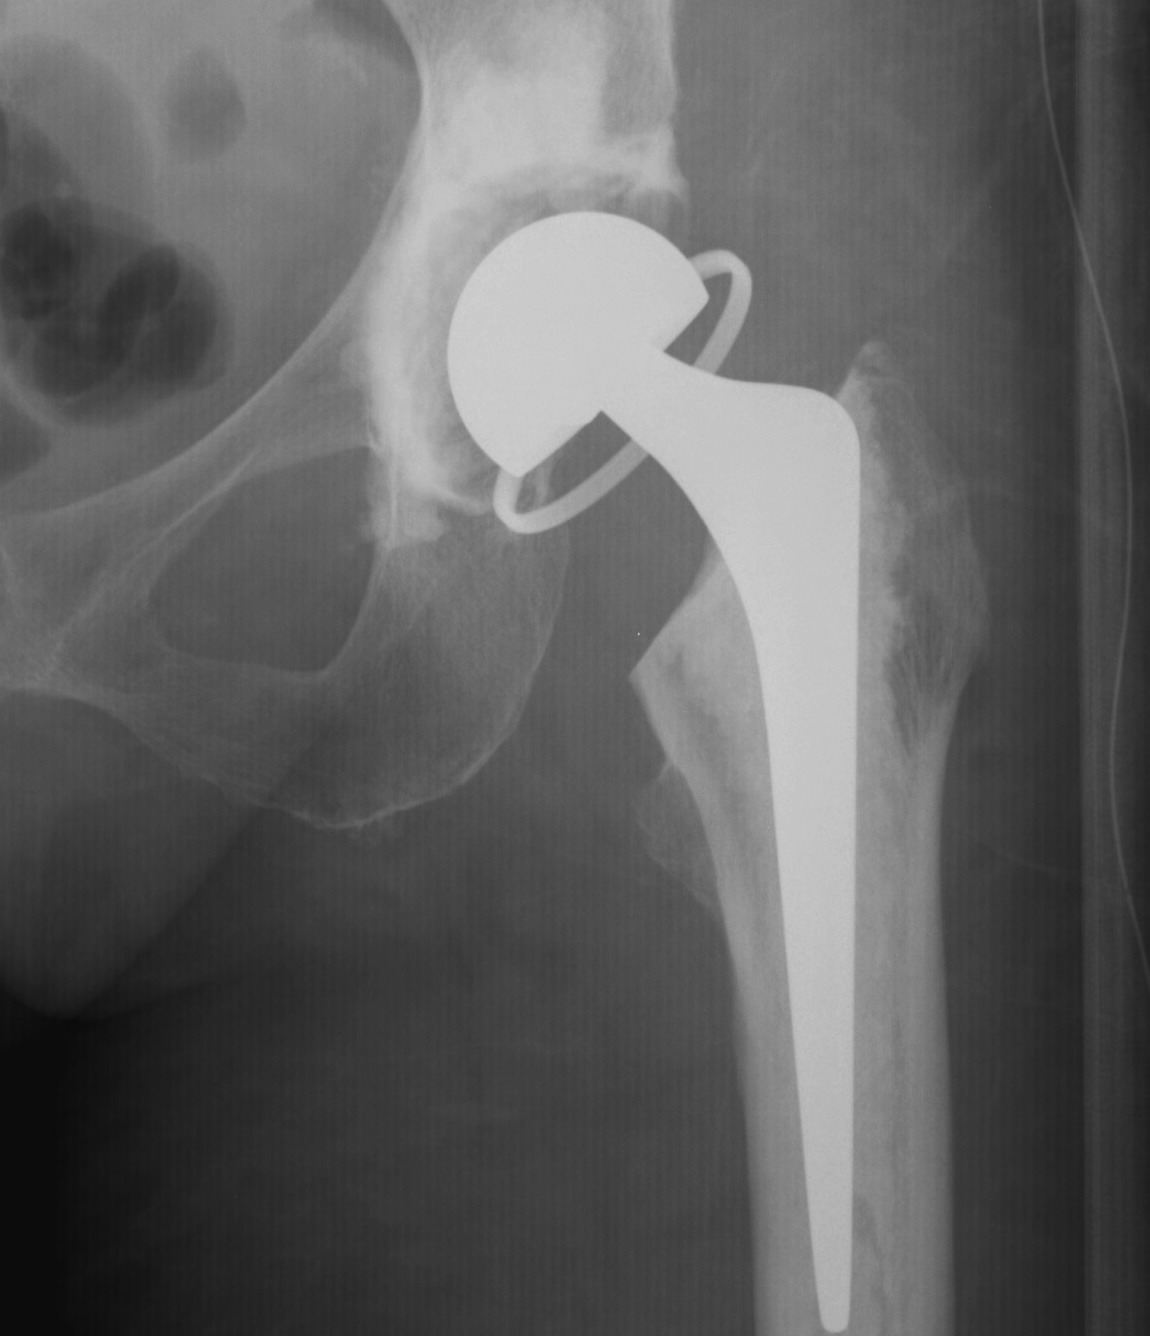

Dislocated constrained liner

Successful reduction constrained liner

Unsuccessful reduction constrained liner